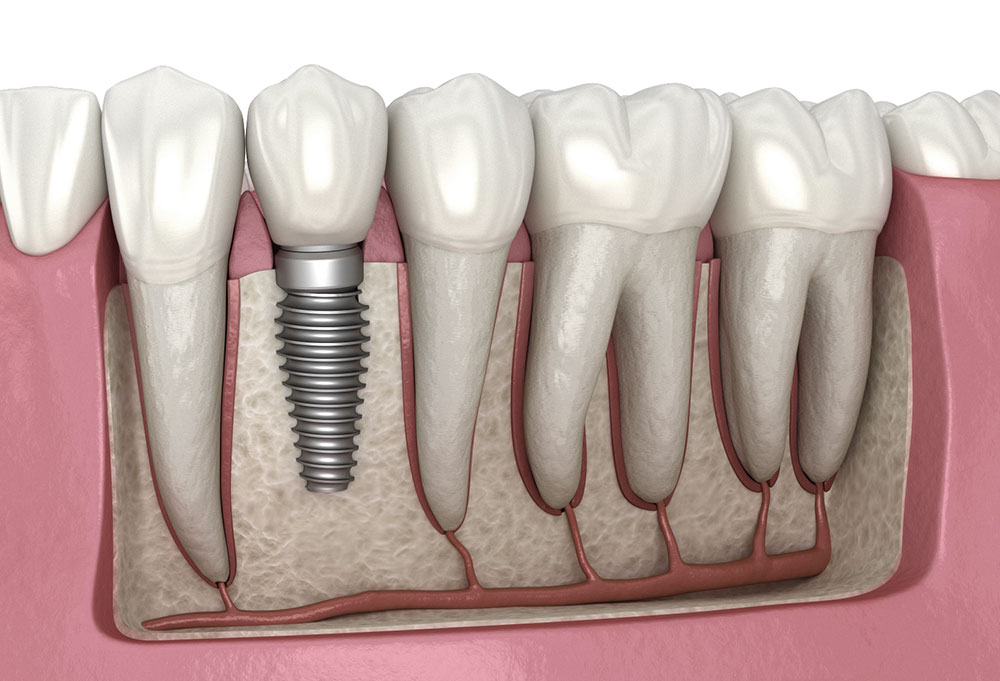

While zirconia gains prominence, titanium remains the gold standard for dental implants. However, modern titanium alloys have undergone substantial improvements. These enhanced materials feature optimised surface treatments and compositions that promote better osseointegration and long-term stability. The latest generations of titanium implants incorporate nano-surface modifications that accelerate healing and strengthen the bond between implant and bone.

The evolution of implant surface treatments has revolutionised the field of dental implantology. Advanced surface modification techniques now allow for better tissue integration and reduced healing times. These innovations include:

- Hydroxyapatite coatings for enhanced bone formation

- Plasma-sprayed surfaces for improved cellular attachment

- Laser-modified textures for optimal tissue response

- Bioactive glass coatings for accelerated healing